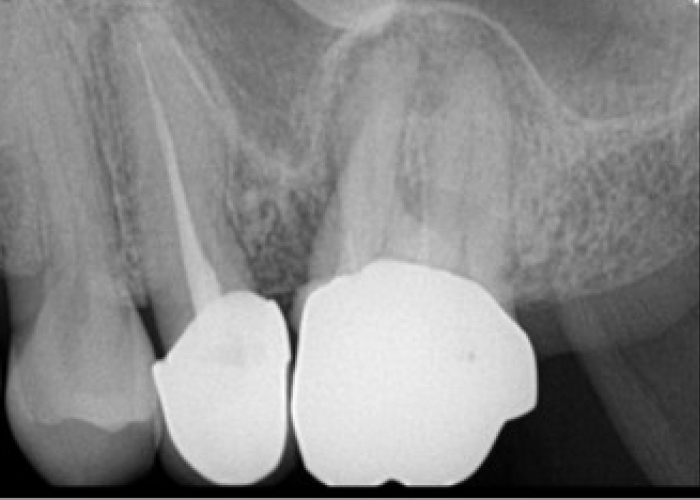

신경치료 전후 사례

• 치료전

치료후